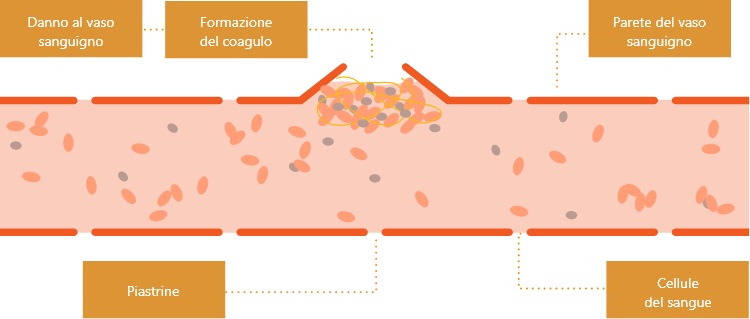

I vasi sanguigni portano il sangue anche ai muscoli e ai tessuti che circondano le articolazioni. Nel sangue sono presenti diversi fattori della coagulazione, inclusi il FIX e il FVIII.

Quando un vaso sanguigno è danneggiato, il sangue può fuoriuscire: questo fenomeno è noto come “sanguinamento”. Parliamo invece di “microsanguinamenti” quando il fenomeno coinvolge piccole quantità di sangue e spesso può passare inosservato o non causare dolore.

Quando si verifica un sanguinamento, si attiva un processo che coinvolge i fattori della coagulazione e cellule del sangue specializzate chiamate piastrine. Le piastrine, con la coagulazione, bloccano il sanguinamento.

In assenza di emofilia, una volta terminato il processo di coagulazione, il coagulo, copre il sito della lesione, bloccando la parete del vaso danneggiato per fermare il sanguinamento e consente al vaso sanguigno di ripararsi.